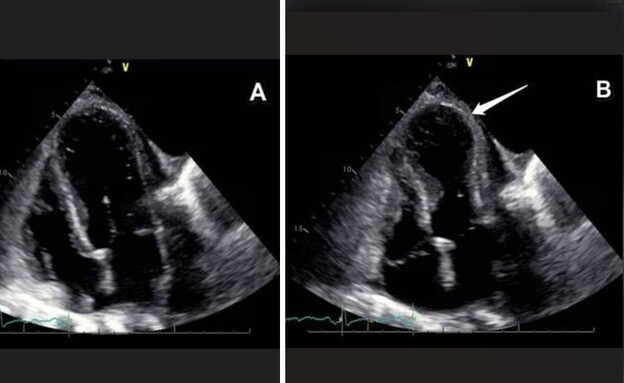

ככה זה נראה בגוף: התופעה הבריאותית שהשתלטה על ישראל אחרי 7.10